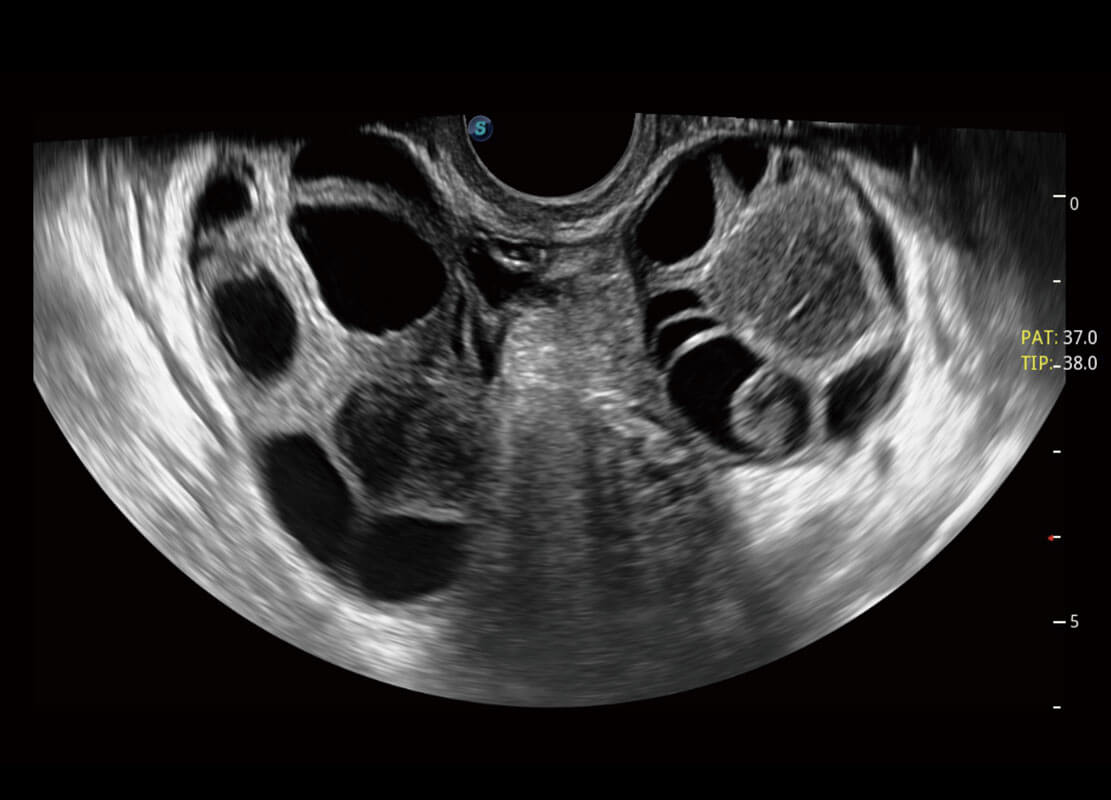

P60優(yōu)異的圖像質(zhì)量搭載專(zhuān)科探頭,在婦科基礎(chǔ)疾病的診斷、卵泡生長(zhǎng)的監(jiān)測(cè)、輸卵管通暢情況的判別等方面為您提供生殖應(yīng)用方案。

腔內(nèi)婦科-宮腔分離

腔內(nèi)婦科-卵巢

腔內(nèi)三維-宮內(nèi)節(jié)育器

腔內(nèi)三維-光影成像